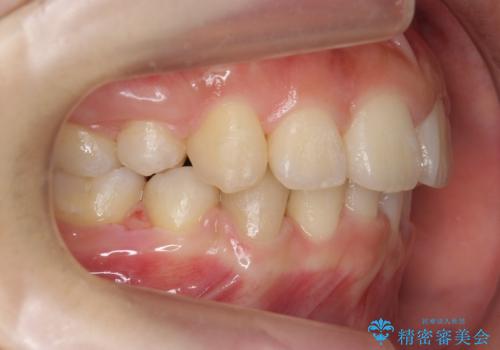

20代女性 出っ歯 口元を引っ込めたい

口元を下げたいとのことで、歯を抜いてワイヤー矯正を行いました。

口元、横顔の変化については、美容整形よりもゆっくりとした自然な変化が期待できます。

上下左右の小臼歯を抜歯しています。